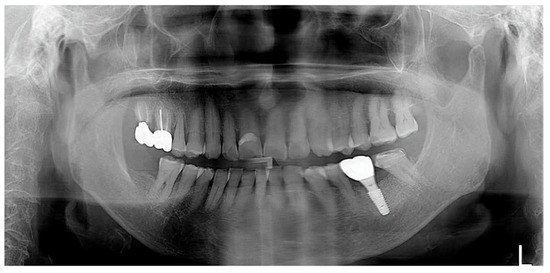

As part of a maintenance therapy program for the patient, a follow-up examination was performed every 6 months and the patient underwent dental plaque control. Additional periodontal treatment was performed when necessary in additional appointments. In addition, panoramic radiographs were taken every year to evaluate the prognosis of the implant. A 3-year follow-up examination showed successful maintenance of the implant prosthesis in the oral cavity (Figure 7).

For this patient, the same periodontal maintenance protocol the patient received in case 1 was performed. Implant prosthesis was successfully maintained at the 3-year follow-up examination (Figure 12).

Figure 7. Panoramic radiograph after 3 years of delivery.

Figure 12. Panoramic radiograph after 3 years of delivery.